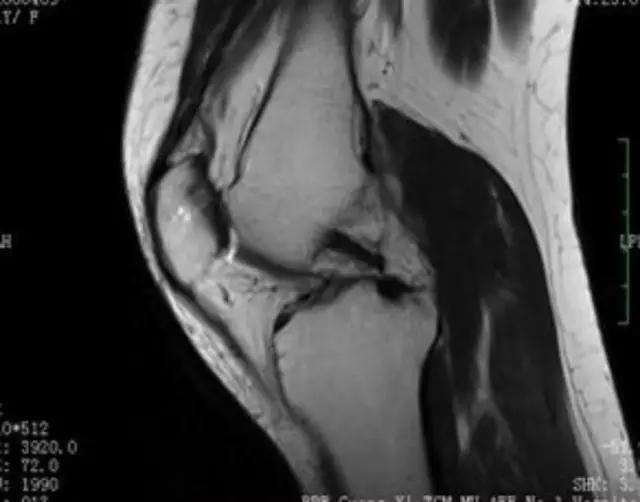

下图是同一个病人的MRI照片,MRI显示的内容更多,包括骨与软组织等,很多早期的、细微的病变都能清晰显示,其诊断报告对病人造成的影响也更大!

我们可能都不熟悉T1、T2,怎么办?当我们发现有问题后,利用照片上图像的对比,推测病变的可能也是一种诊断方法。病例:黄XX,女,39岁,左膝关节反复交锁1年。图1:肿物信号与骨信号一样图2:肿物信号与骨信号一样图3:肿物信号与骨信号不一样 肿物应该与骨相关,但不是骨性,推断:膝关节滑膜软骨瘤。手术后得到证实。